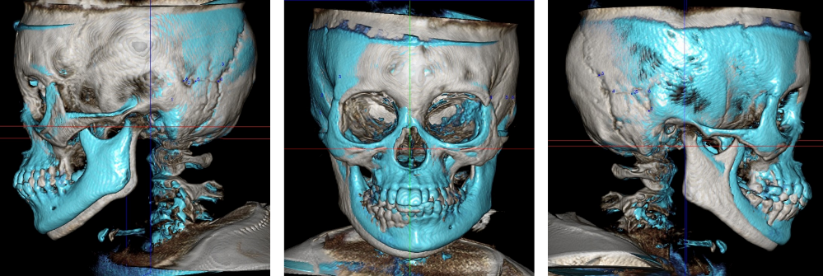

【CTによる骨格の変化】

※左:RAMPAの装着時間が足りないと、赤矢印の限られた部分の変化になってしまいますが、

装着時間を守ることで、青丸のように中顔面全体が上前方へと成長します。中顔面が上前方へ成長することで、下顎も回転するように上がり、物理的に圧迫されていた気道が拡がります。

【治療前後の骨格形態の比較】(青色がRAMPAによって変化した部分)